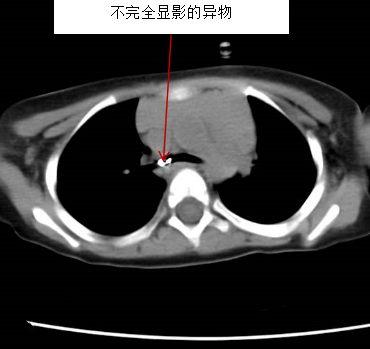

值班护士通知麻醉医生后,立刻行动起来:孩子小,提高手术间温度,准备异物取出器械,清点微型异物钳,调试支气管镜设备,为了节约时间,铺设无菌手术台……刚准备结束,手术室的门铃就被按响了。耳鼻喉科檀子峤医生直接将患儿及家属送至手术室门口,一位爸爸抱着孩子,妈妈紧随其后,两人眼睛都哭红了,声音抖得不成样子:“求求你们救救孩子!他把灯珠吸进去了,憋得喘不上气了!”1岁8个月孩子,小小的身子蜷缩着,眉头拧成一团,脸色苍白,每一次呼吸都带着尖锐的喘鸣。檀子峤快速交代病情:“胸部CT显示气管内有带铁丝的灯珠异物,双肺有渗出,确诊气管异物、支气管异物合并吸入性肺炎,随时可能窒息,必须立刻手术!”手术室值班护士边安抚着患儿及家长,并核对患儿信息和禁饮食时间,麻醉科刘卫东主任医师和耳鼻喉科冯亚茹医生也第一时间赶到,并快速完成了交班将患儿迅速转运至手术间。